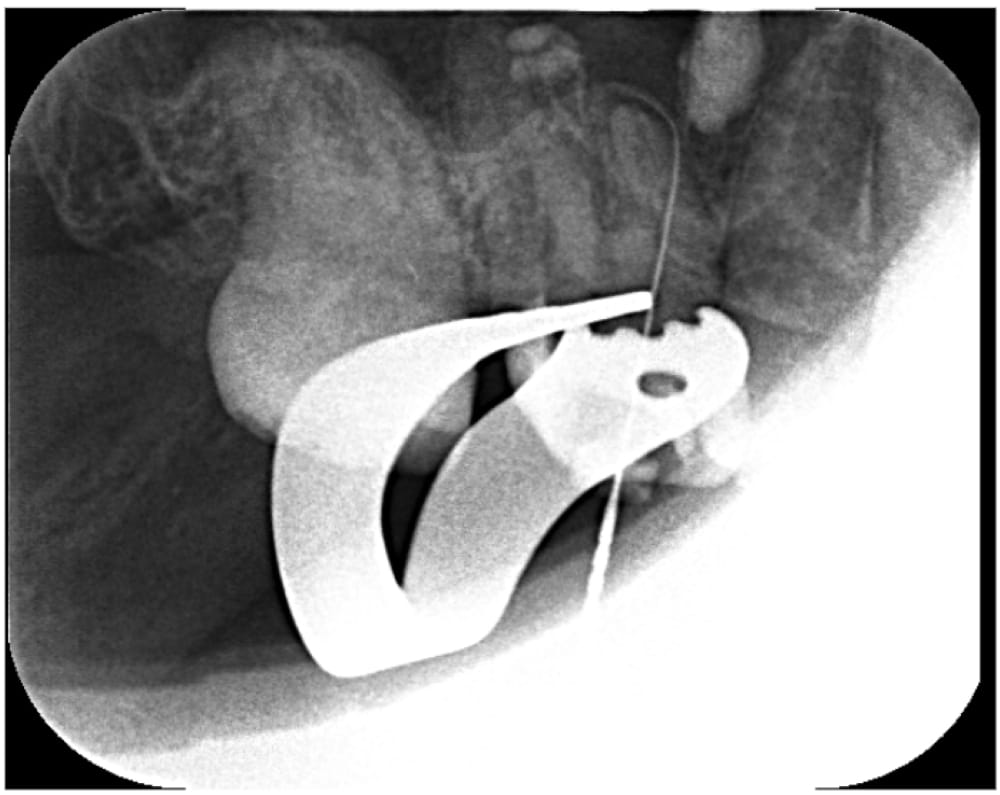

根管内の古い詰め物をすべて除去し、本来の異なる方向に穴があいているパーフォレーション部位に対しては、MTAセメントを使用して穿孔封鎖を行いました。

治療は2回で完了し、飛び出ている材料の状態も含め、経過観察となりました。